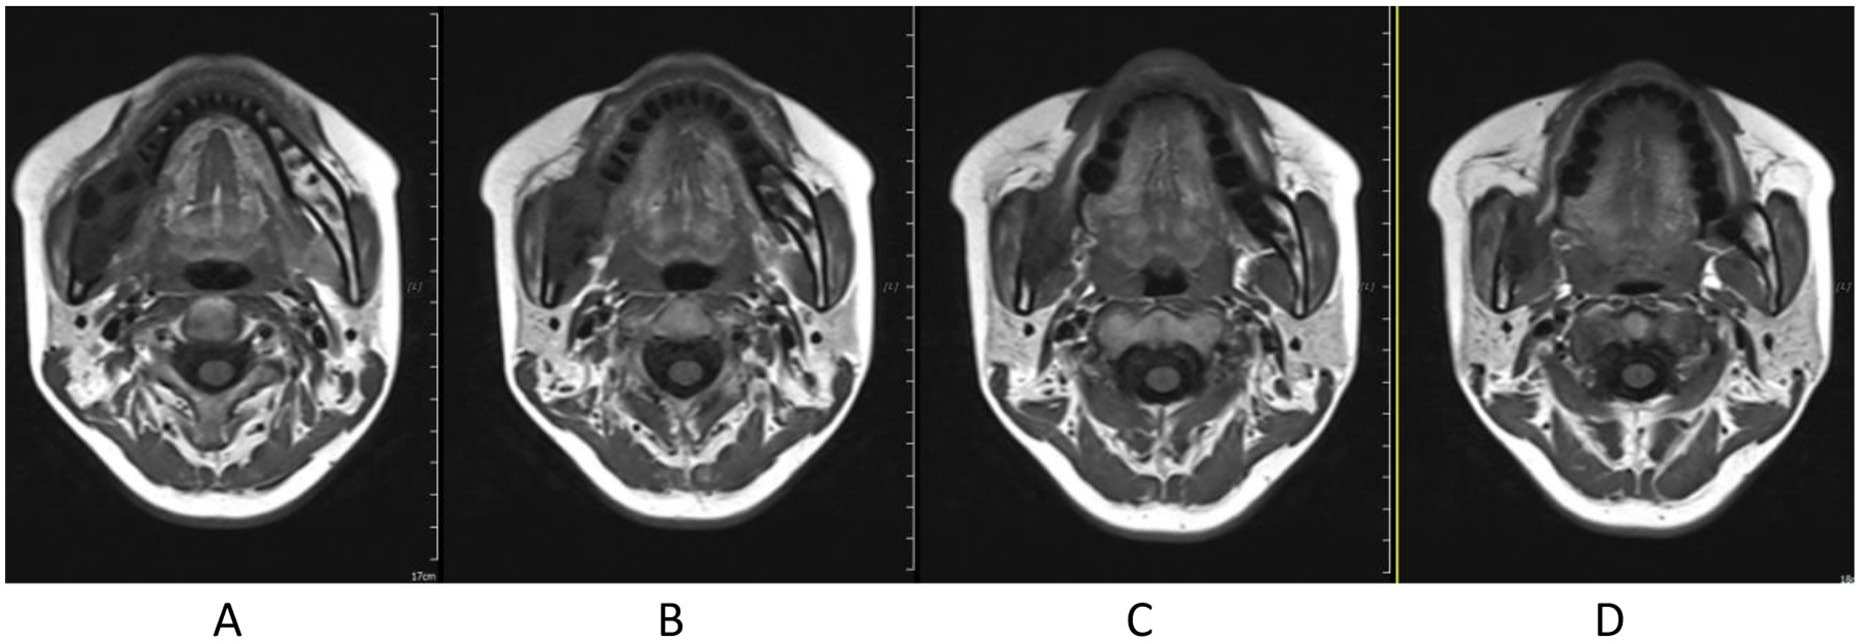

Treatment was tolerated well. During and after CIRT, there was only grade 2 skin (Figure 2) and oral mucosa acute adverse event, and no grade ⩾3 RTOG acute effect. During and after CIRT, her pain in the right mandible is continued but never aggravated, but painkiller is not needed; 6-month post completion of radiotherapy, she was in a very good clinical state, and the pain in the right mandible resolved completely. One to three months after CIRT, there were no significant changes of tumor size on MRI (Figures 3–6), just intensity of contract enhancement gradually diminished on contract-enhanced T1-weighted MRI; from 6months on, the size of the tumor decreased gradually (Figure 7); up to 16months after CIRT, it regressed to 3.6cm×3.2cm×1.7cm; and on 19months after CIRT, it regressed to 3.6cm×3.2cm×1.7cm, and the efficacy evaluation is PR (partial response) (Figures 8–10).

Figure 5. 1 month after CIRT.

Figure 6. 3 months after CIRT.